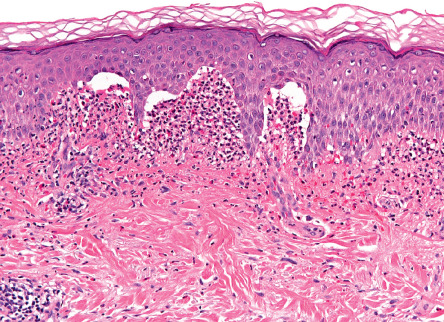

Pathology

For routine histology, it is optimal to capture a small, intact vesicle. If this is not available, an area of erythema should be biopsied. Areas of erythema will show dermal papillary edema and neutrophil infiltration associated with a superficial perivascular lymphocytic infiltrate. Dermal papillae filled with neutrophils, with relative sparing of the lowermost tips of the intervening rete ridges, is a characteristic finding. When an intact vesicle is biopsied, a subepidermal blister containing predominantly neutrophils will be seen ( Fig. 31.4 ).